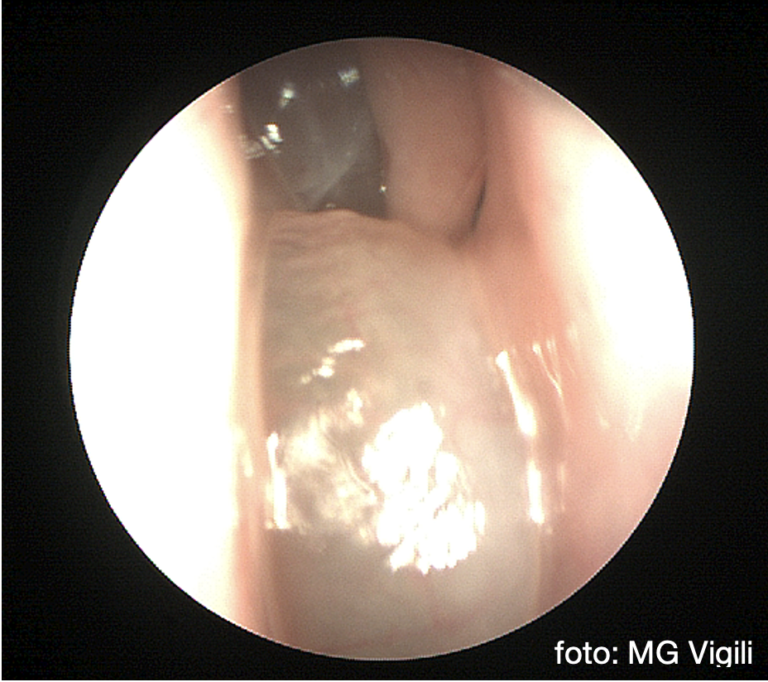

Eosinofilia periferica elevata è fattore prognostico di recidive di sinusite cronica polipoide